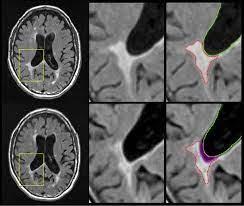

Advanced MRI biomarkers for MS progression

Changes in brainvolume are predictive of clinical and

disability status in CIS, RRMS, and PPMS

Advanced Imaging biomarkers for MS progression

Chronic pathology within existing lesions slowly expanding/evolving lesions

Microglial activation

transfer ratio1, 7 Tesla MRI2 , Deformation-based (Jacobian) analysis using conventional T2- and T1- weighted images3 , susceptibility-weighted imaging (SWI)4 and quantitative susceptibility mapping (QSM)4